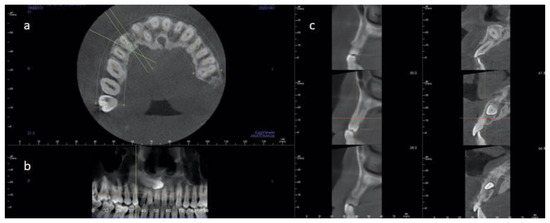

2.1.1. Case 1

2.1.2. Case 2